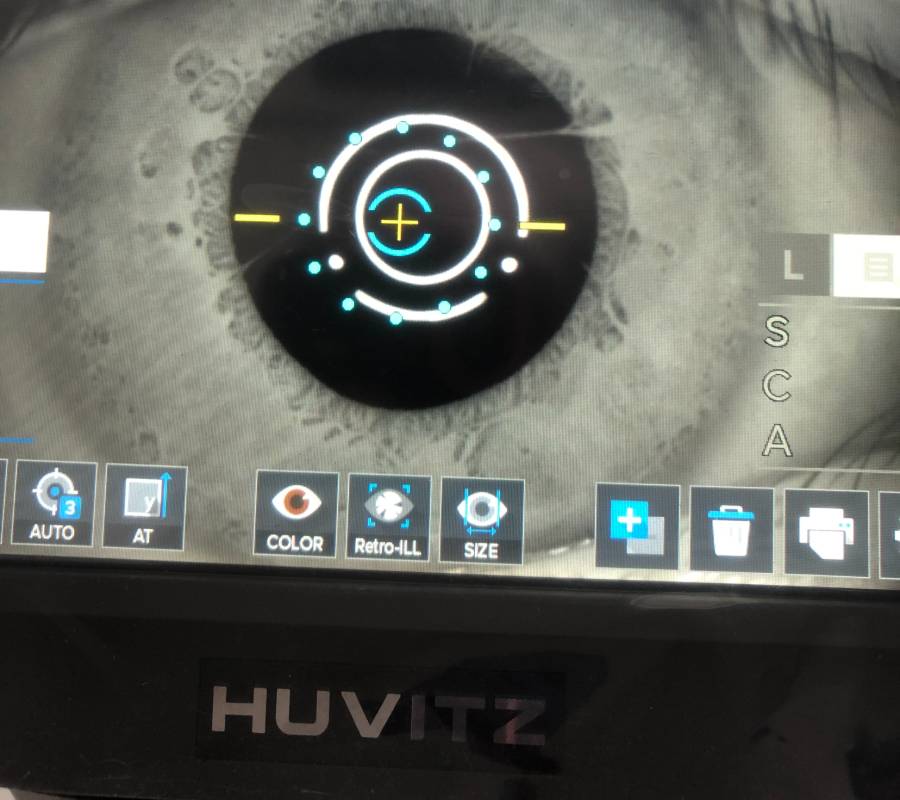

Pemeriksaan menyeluruh ke atas bahagian hadapan (anterior) dan belakang (posterior) mata—termasuk kornea, kanta, iris, retina serta saraf optik.